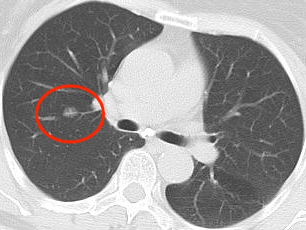

近年来,贵州航天医院各科室紧跟医学前沿,不断强技术、补短板,大力开展新技术、新项目,完成了许多高精尖、高难度、本地区“首例”的技术,填补了医院医疗技术空白,满足了群众日益增长的医疗需求。 贵州航天医院呼吸与危重症医学科是贵州省内呼吸疾病治疗规模最大,诊疗项目最全的呼吸疾病品牌科室,呼吸介入技术达到了全国先进水平,在贵州省内处于领先的地位。 本期,我们将为大家带来呼吸与危重症医学科特色技术——氩氦刀冷冻消融技术治疗肺癌、高危肺结节。 案例分享 患者在体检时发现右肺结节(10mm),就诊于当地我院一专科联盟合作医院,但因当地医疗条件有限,患者通过专科联盟绿色通道前往我院就诊,入院后,通过经皮肺穿刺活检,病理诊断为右肺原位腺癌,科室立即组织专家开展肺结节多学科会诊(MDT),为患者制定诊疗方案。 经充分的沟通下,患者及家属拒绝手术切除。科室再次严格讨论评估,患者情况满足氩氦刀冷冻消融术指征,再次将治疗方案与患者及家属沟通同意后,为患者制定并成功实施氩氦刀冷冻消融术。 冷冻消融术中 术后,患者定期复查,恢复效果良好。 术前 术后即刻 术后1月(反应性增大) 术后6月(纤维条索) 术后12月(纤维条索变细) 什么是氩氦刀冷冻消融技术 氩氦刀冷冻消融技术是一种先进的微创超低温冷冻消融肿瘤的医疗技术,它利用氩气和氦气的快速温度变化特性,实现对病变组织的精准冷冻和复温,以达到消融和破坏肿瘤细胞的目的。 氩氦刀冷冻消融技术原理 氩氦刀冷冻消融技术基于焦耳-汤姆逊效应,通过氩气和氦气的快速交换实现局部组织的超低温冷冻(-140℃到-190℃)和快速复温(20℃到45℃),当氩气通过金属杆尖端的蒸发器时,其气压突然降低,会大量吸收周围的热量,使金属杆尖部的气温迅速下降到超低温;随后,氦气在极短的时间内使组织迅速复温,通过热胀冷缩的原理,使肿瘤细胞爆裂。 (一)直接杀伤( 靶区冷冻消融效应) 1.快速冷冻(降温段):细胞内冰晶快速生长并撕裂细胞,导致细胞损坏。 2.慢速冷冻(低温段):细胞外冰晶生长导致水渗出细胞,造成细胞脱水。 3.升温:水迅速进入细胞,导致细胞涨破。 (二)间接杀伤( 冷冻的血管栓塞效应) 病灶区域快速冷热交替,引起微血管细胞脱水、蛋白质变性、微血管损伤、 冰晶及微血栓在微血管内形成,导致血小板聚集、血管栓塞, 局部细胞缺血坏死。 (三)抗肿瘤免疫( 冷冻免疫激活效应) 随着肿瘤细胞的破裂和坏死,促使肿瘤免疫调节因子停止分泌,逆转免疫抑制状态;可调控表面抗原,促进淋巴细胞增殖,提高身体抗肿瘤免疫能力。 氩氦刀冷冻消融技术优势 (一)精准度高:通过精确的靶点定位和温控技术,可实现对病变组织的精准冷冻和复温,避免损伤正常组织。 (二)微创治疗:对周围正常组织的热损伤小,无需开胸开腹,仅有一个针孔,恢复快,几乎无疤痕。 (三)适应症广:肺腺体前驱病变(癌前病变)、甲状腺结节、乳腺结节等;多原发磨玻璃肺结节,因各种原因不适合手术的早期肺癌、肝癌等;内科治疗无法控制的少发转移瘤等。 (四)可重复治疗:由于冷冻治疗对身体的创伤和痛苦较小,可以多次重复进行治疗,这对巨大的肿瘤和多发的肿瘤尤其适用。 (五)无毒性:冷冻治疗是以物理方法杀灭肿瘤,不向体内注射任何药物,避免外科手术、化放疗等对身体带来的巨大创伤和毒副作用,能有效减轻患者肿瘤负荷和痛苦,因此与化放疗、分子靶向药物等治疗方式相比属于无毒治疗。 氩氦刀冷冻消融技术对于早期肺癌、高危结节,可作为手术的替代治疗。对于晚期较大的肿瘤可作为姑息治疗,增强综合治疗的效果,可减少肿瘤负荷,减轻症状,提高生活质量,延长生存时间。 近年来,随着医学影像技术发展和肺癌筛查的广泛开展,肺内结节的检出率显著提高。无论肺内磨玻璃结节还是实性结节,单发或多发,都需要引起重视,定期复查,动态观察结节变化,如有需要请积极治疗。 贵州航天医院 呼吸与危重症医学科专家团队 廖江荣 国务院政府特殊津贴专家、遵义市呼吸疾病临床医学中心学科带头人、二级教授、主任医师 学术任职: 亚洲冷冻治疗学会副主席 第二届中国医药教育协会介入微创专业委员会呼吸分会副主任委员 中国抗癌协会肿瘤微创治疗专业委员会常务委员 中国防痨协会结核病转化医学专业分会常务委员 第一届中国人体健康科技促进会呼吸介入专委会常务委员 中国医疗保健国际交流促进会结核病学分会第三届委员会常务委员 中国抗癌协会肿瘤微创治疗专业委员会粒子治疗学组第四届委员会委员 中国结核病防治综合质量控制专家指导委员会委员 “西部呼吸介入联盟”副理事长 专业擅长: 呼吸系统(肺)疑难病的诊断及危重病的抢救,呼吸系统(肺)感染性、疑难性疾病介入快速诊断(ROSE),尤其在肺癌、肺小结节早期诊断,肺癌微创综合靶向治疗,难治性、复治性、重症肺结核诊疗,硬质支气管下复杂性气道狭窄诊治,纤支镜介入治疗气道肿瘤、结核、气道狭窄(球囊扩张、支架植入、高频电刀、氩气刀、冷冻、灌洗、注药、微波消融),间质性肺疾病的诊疗上具有极高水平;带领团队勇于创新,在贵州省率先开展多项新技术、新疗法,如CT引导下及纤支镜下I125粒子植入及CT引导下微波、冷冻消融介入治疗肺癌等多项新技术,带动了贵州省肺部疾病的介入治疗水平提高。 唐永江 四川大学华西医院 呼吸与危重症医学科 副主任医师 呼吸危重症医疗组长 香港中文大学博士 美国康奈尔大学访问学者 贵州航天医院 呼吸与危重症医学科 学科带头人 主要从事呼吸危重症(特别是呼吸重症感染)的临床及科研工作。 PCCM专培结业医师 中华医学会呼吸病学分会呼吸危重症学组秘书 中华医学会呼吸病学分会ECMO工作组成员 四川省医学会呼吸病学专委会介入学组委员兼秘书 发表文章20余篇,主持及参与多项国家自然科学基金及省卫健委基金。 蒋 婷 呼吸、感染党支部书记,呼吸与危重症医学科主任,副主任医师 专业擅长:从医20余年,在呼吸系统疾病、介入呼吸病学、肺部结核、肺部肿瘤等方面具有丰富的临床经验和专业技能,尤其是慢性阻塞性肺疾病、支气管扩张、肺结核、耐药肺结核、肺癌、胸腔积液等肺部疾病的诊治、微创介入、危重病患者抢救。 现任中国防痨协会人兽共患结核病专业分会委员,中国女医师协会第一届介入专业委员会委员,贵州省基层呼吸疾病防治联盟-间质性肺疾病联盟委员,贵州省防痨协会第七届理事会理事,贵州省中西医结合学会呼吸专业委员介入呼吸病学组委员,贵州省遵义市中医药学会中西医结合肺病(呼吸)分会副主任委员,贵州省遵义市中医药学会中医肿瘤专业委员会常委;发表论文数篇,参与并主持多项科研项目。 王 云 中共党员,呼吸与危重症医学科一病区副主任,副主任医师 专业擅长:擅长呼吸系统常见病及疑难危重症、介入呼吸病学、肺部肿瘤疾病的诊治,尤其擅长快速现场评价(ROSE)技术。 贵州省中西医结合学会呼吸专业委员会介入呼吸病学组委员,遵义市中医药学会中西医结合肺病(呼吸)分会委员,贵州省中西医结合学会第六届呼吸专业委员会委员。 李桂凤 中共党员,呼吸与危重症医学科三病区主任,副主任医师 专业擅长:从事呼吸系统疾病、结核病学、介入呼吸病学、肿瘤综合治疗、呼吸康复等临床工作20余年,擅长呼吸内科常见病、多发病及疑难重症危重病症的诊治,尤其对重症疑难结核及耐药结核病、介入治疗(肺)呼吸系统疾病、呼吸危重病抢救等方面具有较高诊疗水平。 中国防痨协会非结核病专业委员会委员,贵州省中西医结合学会第六届呼吸专业委员会委员,贵州省康复学会睡眠障碍康复专业委员会委员,遵义市呼吸内科医疗质量控制中心委员,遵义市落实民生实事结核病筛查阅片专家组成员;主持及参与实用新型专利3项。 周裕祥 中共党员,呼吸与危重症医学科四病区主任,副主任医师 专业擅长:经皮肺介入、经血管介入诊疗技术。 贵州省中西医结合学会呼吸专业委员会介入呼吸病学组常务委员,中国医师协会呼吸医师分会介入呼吸病学工作委员会呼吸病血管介入学组委员,贵州省中西医结合学会呼吸学分会委员,遵义市医学会放射肿瘤治疗学分会委员,中国医药教育协会介入微创呼吸分会委员,北京健康促进会中青年专家委员会胸部疾病精准活检分委会委员;曾赴重庆医科大学RICU、珠海市人民医院介入科进修学习。 杨 芳 中共党员,呼吸与危重症医学科内镜中心主任,副主任医师 专业擅长:从事临床工作约20年,对呼吸危重病的救治有独到的见解,尤其擅长呼吸系统疾病的介入诊疗,对呼吸内镜下的诊治及经皮肺穿刺诊疗技术具有丰富的临床经验。 亚洲冷冻治疗学会委员,中国医药教育协会介入微创呼吸分会委员,西南结核病医院联盟第二届委员会秘书/委员,贵州省中西医结合学会第六届呼吸科专业委员会委员,贵州省中西医结合学会呼吸专业委员会介入呼吸病学组秘书,贵州省中西医结合学会呼吸专业委员会基层康复学组副组长,贵州水利电力医学科学技术会高原医学分会委员,遵义市中医院学会中西医结合肺病(呼吸)分会秘书/常务委员,遵义市医学会肿瘤学分会(第二届)委员,遵义市医学会放射肿瘤治疗学分会第二届委员;主持及参与科研课题多项,参编著作《呼吸内镜操作技术规范》、《介入结核病学》,发表论文数篇。 贵州航天医院 呼吸与危重症医学科简介 贵州航天医院呼吸与危重症医学科以呼吸危重症和介入呼吸病学为强力推手,以肺部感染性疾病及肺癌、肺小结节的早期精准诊疗、慢性呼吸疾病康复治疗为特色,以人才团队建设为核心的科室发展模式,现已成为贵州省内呼吸疾病治疗规模最大、诊疗项目最全的呼吸疾病品牌科室。是贵州省医学重点学科、临床医学重点专科建设单位,遵义市首批呼吸重点学科、重点专科建设单位。是国家卫健委能力建设和继续教育肿瘤微创介入建设中心、贵州省县级医院微创介入培训中心、遵义市呼吸疾病临床医学中心。是国家呼吸医疗质量控制与管理哨点医院、遵义市呼吸内科专业医疗质量控制中心。是中国医药教育协会介入微创呼吸分会呼吸介入技术培训中心单位;国家卫健委海医会呼吸分会ROSE专委会“诊断性介入肺脏病学快速现场评价”培训基地;中国肺癌防治联盟“贵州航天医院肺结节诊治”分中心,中国人体健康科技促进会呼吸介入技术培训基地,贵州省中西医结合会呼吸学分会呼吸介入专委会主委单位。 基本情况 平均每年开展气管镜诊疗约4000例,经皮肺穿刺介入诊疗近千例,开展的项目包括经支气管镜(软、硬)下冷冻、氩气刀、高频电刀、球囊扩张、支架置入、超声内镜诊疗等气道介入诊疗技术,经皮肺穿刺活检及肿瘤消融术(微波、冷冻)、ROSE技术、内科胸腔镜诊疗及经血管介入诊疗技术,且多项呼吸介入诊疗技术在省内处于领先水平。 诊疗范围 专科擅长:致力于呼吸系统感染性、疑难性疾病的介入快速精准诊疗;肺癌与肺小结节早期精准诊疗水平项目提升。擅长呼吸系统(肺)疑难病的诊断及危重病的救治,尤其是肺癌、肺小结节的早期诊断,肺癌综合靶向治疗,肺结核综合诊疗等肺部疾病的介入诊疗在贵州省内处于前沿水平。 肺结节MDT门诊 贵州航天医院呼吸与危重症医学科微创介入诊疗技术已达到国内前列,省内领先水平,是亚洲冷冻治疗学会常务理事单位,并获批成立遵义市肺结节多学科(MDT)微创诊疗中心。 出诊信息 出诊时间: 周一至周五 8:00--12:00;14:00--17:00 出诊地点: 遵义市肺结节多学科微创诊疗中心(MDT)门诊(贵州航天医院呼吸综合楼1楼) 呼吸与危重症医学科与心胸外科、医学影像科、麻醉科等科室建立了多学科(MDT)会诊机制,结合患者情况,通过采取外科手术、冷、热消融等多种治疗手段,帮助患者安全、有效、精准、科学、快速治疗肺结节,单次消融手术时间约半小时左右,几乎没有疼痛,且并发症少,3-5天即可出院,有效减少了患者因开刀手术需长时间恢复的痛苦。 一审一校:周裕祥、黄成成